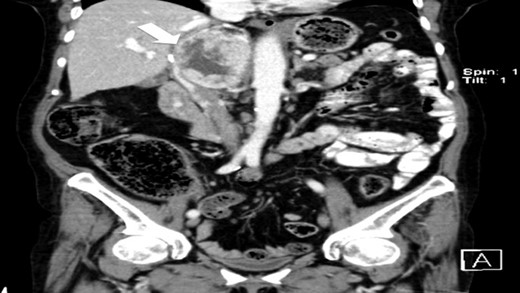

The authors report a case of a 64-year-old female, with no relevant family history and a past medical history of recently diagnosed supraventricular tachycardia, arterial hypertension, type 2 diabetes mellitus, euthyroid multinodular goiter and chronic venous insufficiency. She was referred to our Institution from other Hospital where she went due to paroxysms of palpitations, headache and diaphoresis, that led to biochemical investigation that was remarkable for: total plasmatic cathecolamines: 73 747 ng/L (normal range (NR) <598 ng/L), plasmatic noradrenaline: 73 589 ng/L (NR <420 ng/L), adrenaline: 130 ng/L (NR <84 ng/L), plasmatic dopamine: 28 ng/L (NR <94ng/L), aldosterone: 87,5 ng/dL (NR 4–31 ng/dL), plasmatic renin activity: 33 ng/mL/h (NR 0,5–4 ng/mL/h), Vanylmandelic acid: 39,2 mg/24 h (NR <13,6 mg/24 h). Abdominal contrast enhanced CT scan revealed a large (70 × 35×78 mm3), hyperdense (20 HU) right adrenal mass. Abdominal magnetic resonance (MRI) also described an adrenal mass with 66×33 mm2, suggestive of pheocromocitoma (slightly hypointense on T1 and markedly hyperintense on T2 weighted imaging). No vascular nor locoreginal lymph node involvement were found and the left adrenal was radiologically normal. The patient underwent genetic testing with next generation sequencing, that excluded mutations of the succinate dehydrogenase (SDHB, C, D and A), MEN2, VHL, Neurofibromatosis type 1 genes. Genetic testing for MAX and TMEM127 were not performed due to institutional unavailability. Pre-operative pharmacological therapy was initiated with phenoxybenzamine (10 mg twice a day), followed by bisoprolol (20 mg/day) and amlodipine (5 mg/day), which rendered the patient fit for surgery. The patient underwent transperitoneal laparoscopic right adrenalectomy. Intraoperatively, a hipervascularized right adrenal gland with adhesions to the upper pole of the kidney was identified and excised, with no complications recorded. In the immediate post-operative period, antihypertensive drugs were stopped and blood pressure remained normal until the second post-operative day, when hypertension and tachycardia recurred, leading to urinary metanephrine reevaluation on the 10th post-operative day. The results were highly suggestive of disease persistence (urinary normetanephrines >10 500 ng/L (NR <600 ng/L)). Histology revealed no signs of neoplasia. Abdominal CT scan revealed the persistence of a solid heterogeneous nodule, with 70 × 49 × 87 mm3 (AP × T × L) adjacent to upper right renal pole, with peripheral contrast enhancement and central necrosis (Figs 1–3). This findings suggested abdominal paraganglioma (of the organ of Zuckerkandl). Due to the higher malignant potential of paragangliomas, an 123I-MIBG scintigraphy was performed, excluding metastatic disease.

CT scan (axial) of the heterogenous solid nodule with 70 × 49 × 87 mm3 with peripheral contrast enhancement and central necrosis (white arrow).

CT scan (coronal) of the heterogenous solid nodule (white arrow).